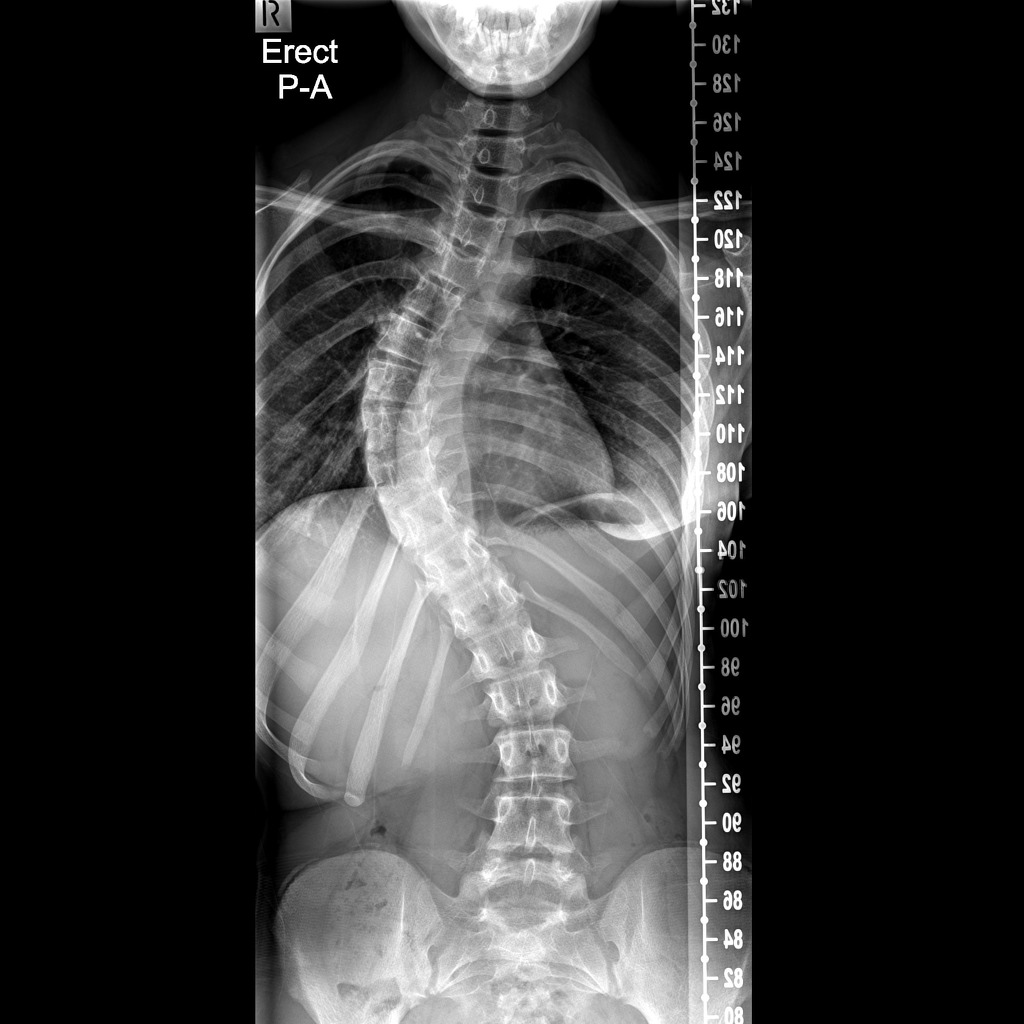

Coba deh, paling ngga periksa sendiri di depan cermin ya, jangan2 ada scoliosis/punggung bengkok. Kalo ragu bisa periksa ke dokter utk dipastikan tulang belakangnya bagus/bengkok

Jadi kasus punggung bengkok/scoliosis ini banyak banget, dan sebagian besar kasusnya tidak terdiagnosis karena seringkali gejalanya ringan(cuma gampang pegel).

Sering juga orang yg menderita tidak menyadarinya, dan ketahuan secara kebetulan saat medical check up.

Kasus scoliosis memang lebih banyak pada wanita, untuk bengkok yang signifikan, bahkan sampai 10 : 1 perbandingan kejadiannya. lebih sering pada wanita dibanding pada laki2.